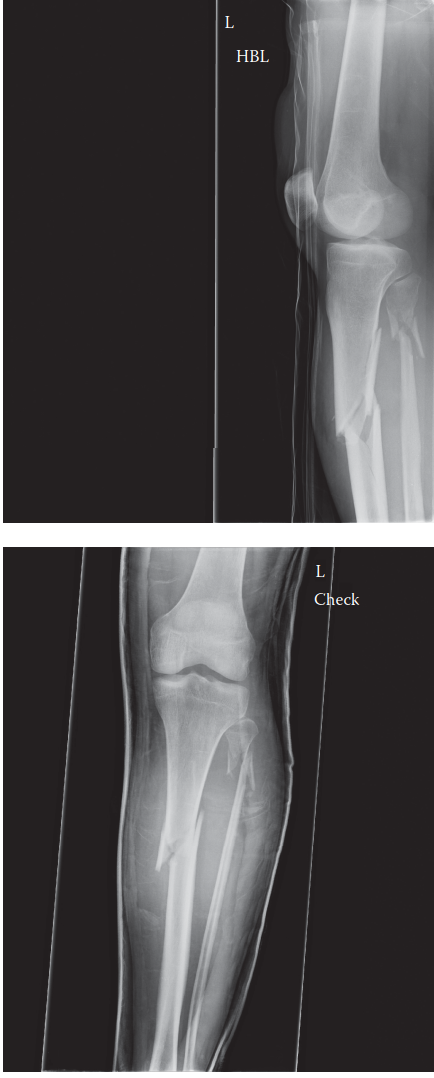

. Can you describe the radiographs? These are AP and lateral radiographs of the left tibia and fibula showing…